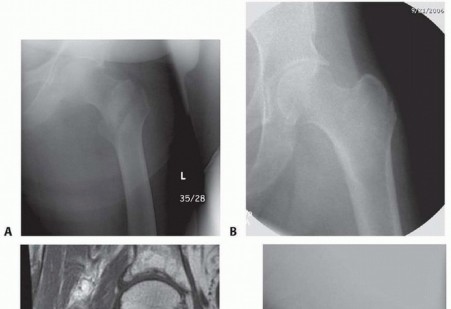

DEFINITION Periprosthetic fractures about a total hip arthroplasty are fractures which occur in the femur or …

DEFINITION Peritrochanteric hip fractures are defined as extracapsular hip fractures, always involving the tr…

DEFINITION Fractures of the proximal humerus can be two, three, or four part according to the Neer classifica…

DEFINITION Proximal humerus fractures are defined as those of the proximal portion of the humerus involving t…